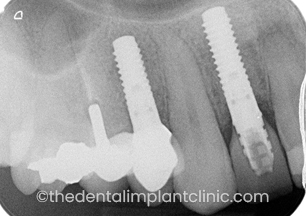

Implant placement to replace single missing teeth. In this instance, the teeth that were missing are the patients upper right first premolar (UR4) and lateral incisor (UR2) teeth.

X-Ray of Implants placed at UR2 and UR4 sites